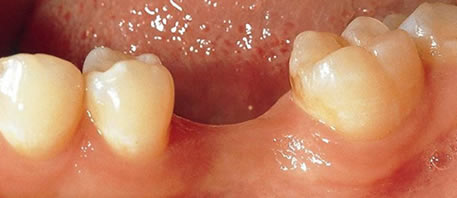

Before Dental Implant

dental implants northern ireland

After Dental Implant